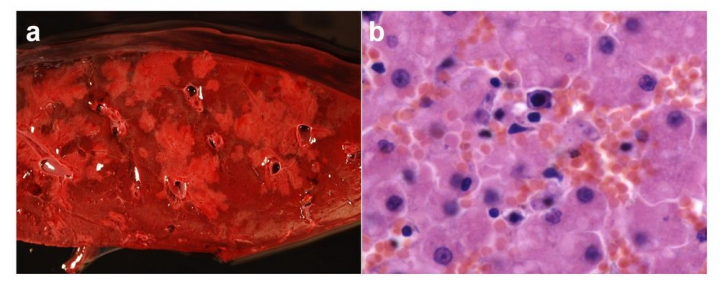

Según la primera clasificación, el 66,7% de los animales murieron por causas no relacionadas con la intervención humana, como lesiones traumáticas (peleas, infanticidio…), hepatitis infecciosa canina, clostridiosis o neoplasia, entre otras. El 33,3% restante murió por causas directamente relacionadas con la intervención humana como la caza ilegal (por arma de fuego o lazo), envenenamiento o miopatía por estrés.

Si tenemos en cuenta la etiología, el 57,1% de los animales murieron por causas no infecciosas y el 42,9% por causas con etiología infecciosa como hepatitis infecciosa canina o miositis gangrenosa provocada en la mayoría de los casos por Clostridium sordellii.

Con nuestro estudio queda patente que el hombre todavía es responsable de algunas muertes de osos, aunque afortunadamente esta tendencia ha ido disminuyendo. Sin embargo, el hecho de que un alto porcentaje de los animales fallezcan por infecciones es de gran relevancia y contrasta con los datos de causa de muerte anteriormente descritos para otras poblaciones de estos animales a nivel mundial, donde las enfermedades infecciosas en ningún caso se describen como un motivo de fallecimiento importante.

El origen de la hepatitis canina infecciosa en los úrsidos es desconocido. Se especula con que podría deberse a una transmisión indirecta a partir de reservorios silvestres o quizá domésticos. Hay que tener en cuenta que el virus se excreta en orina, heces y exudados nasales y oculares que pueden contaminar el medio ambiente, suponiendo una importante fuente de infección para otros individuos de la misma o diferente especie.

Estudios recientes han demostrado que la infección en el lobo es endémica, y que este comparte la misma cepa vírica que el oso. Se cree que la posible transmisión se produce a partir de perros domésticos no vacunados. Esta vacunación no es obligatoria, y por tanto se hace difícil conocer la situación epidemiológica real de esta infección en el perro.